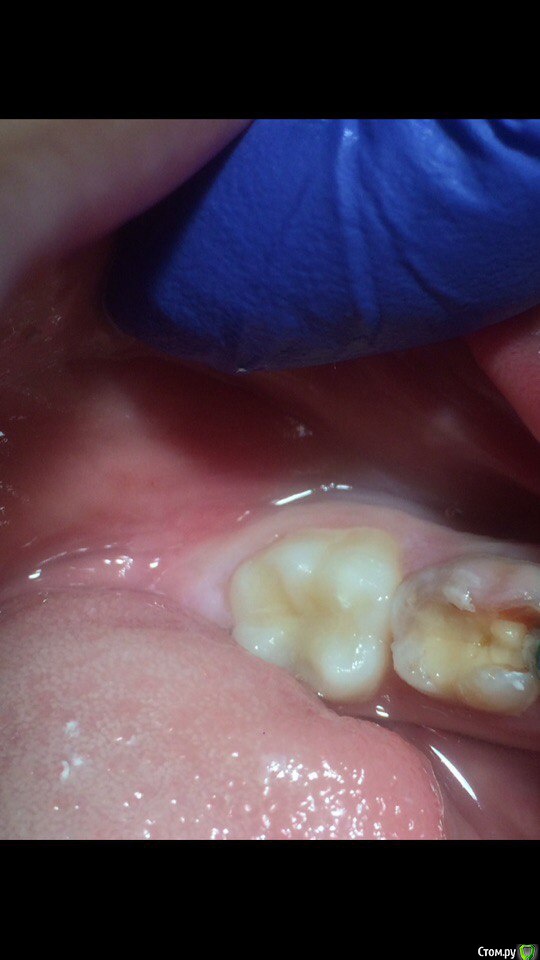

Wrestrus66 Опубликовано 12 октября, 2016 Поделиться Опубликовано 12 октября, 2016 Всем привет..Лечил 36 зуб , Кариес..стрелкой указанно место где очень болезненно , именно в этой точке ..Вопрос какую анестезию вы делаете в таком случае чтоб обезболить ?или же можно его так оставить зондом прошелся как по стеклу , но уже потихоньку зуб начал реагировать на холод но боль быстро проходящая..В итоге я так и оставил мед обработка хг2% , бонд , витример !Говорят витример хорош даже при кариесе , что под ним процесс дальше не пойдет т.к он выделяет Фтор ( не знаю на сколько это правда ) Большая проблема в анестезии Ссылка на комментарий